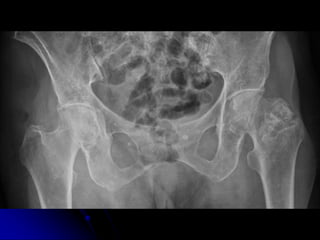

HIP FRACTURES

INCIDENTAL

FINDINGS &

COMORBIDITIES